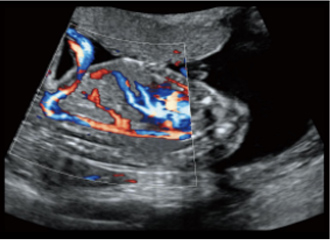

临床图像